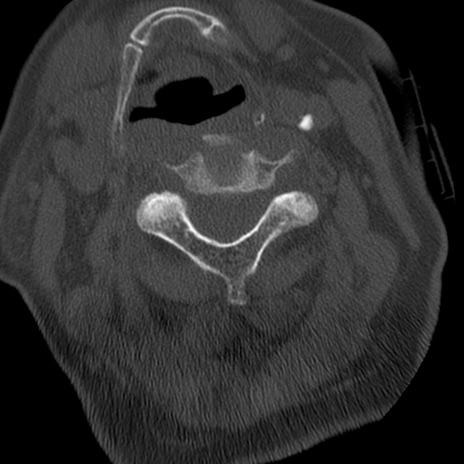

症例50 頚椎CT(横断像)

冠状断像